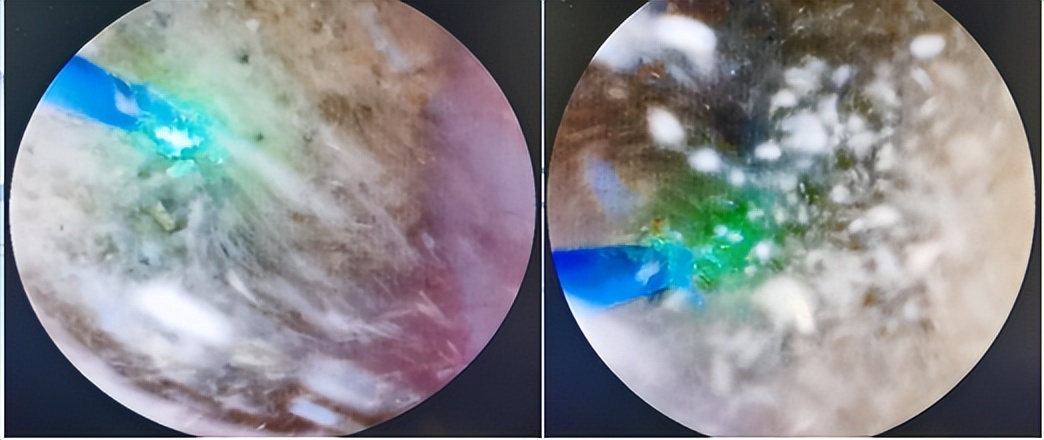

输尿管镜倚仗钬激光光复石地。结石惹钬上身,石亡钬(激光)击。钬激光光纤与软镜虽然一个鼻孔出气,但寄人篱下的光纤却有锐气很任性,刚愎自负,我行我素。软镜内卷光纤不举,软镜躺平光纤出头;软镜光纤常互相拖后腿,导致结石可望而不可击。软镜与光纤需要磨合,方可比翼双飞、治石至终。

石物的品相取决于钬激光的火候。对于质硬、体积较小的结石,推荐高能、低频、短脉宽钬激光碎石模式(钬激光设置通常在0.6-1.0 J和6-10 Hz之间),使结石碎块化成肉丁;对于质软的结石,可以采用低能、高频、长脉宽的模式(0.2–0.6 J和20–80 Hz),只要功夫深,铁石磨成粉。

在与结石的较量中,有好家伙还不够,更需要斗智斗勇。结石爱和软镜玩深沉,怎知软镜套路深,要论窝里斗,没人比他狠。

空手套白狼:分布于各盏的可移动结石,软镜以套石篮引石出洞,生擒到上盏集中营,等待就地正法。

枪挑小梁王:又名“小猫钓鱼”,激光在结石表面钻孔,打入敌人内部,之后将其火线提拔,武装押运入上盏同室操戈。

智取威虎山:专克一卧不起的下盏钉子户。动作要领如下:软镜凌波微步、穿堂入户;拐弯抹角、投机取巧;(结石)欲遮还羞、(软镜)半推半就;激光旁敲侧击、不离不弃;细嚼慢咽、由点到面。输尿管软镜碎石历程跌宕起伏,看懂软镜也就看懂了人生。

鉴于软镜及激光作为肾斗士的杰出表现,太祖赋诗表彰:山高路远坑深,软镜纵横驰奔。石敢横刀立马,激光枪下成仁!